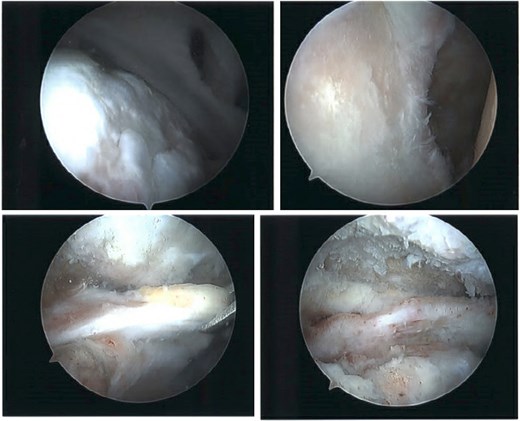

The patient was determined to be a candidate for surgical intervention given his age, ongoing symptoms, and continued dysfunction. Expectations of surgical treatment were discussed, including the possibility of a less reliable outcome regarding his right shoulder given his previous surgical history. Six weeks after injury, the patient underwent left shoulder rotator cuff arthroscopic repair. Findings included full-thickness tears of the subscapularis, supraspinatus, and infraspinatus, with glenohumeral chondromalacia (Fig. 7). He was maintained in a Frank Stubbs immobilizer for 6 weeks and then started physical therapy.

Intraoperative imaging of left shoulder arthroscopic debridement and rotator cuff repair including findings of full-thickness supraspinatus and subscapularis tendon tears, which subsequently were repaired.